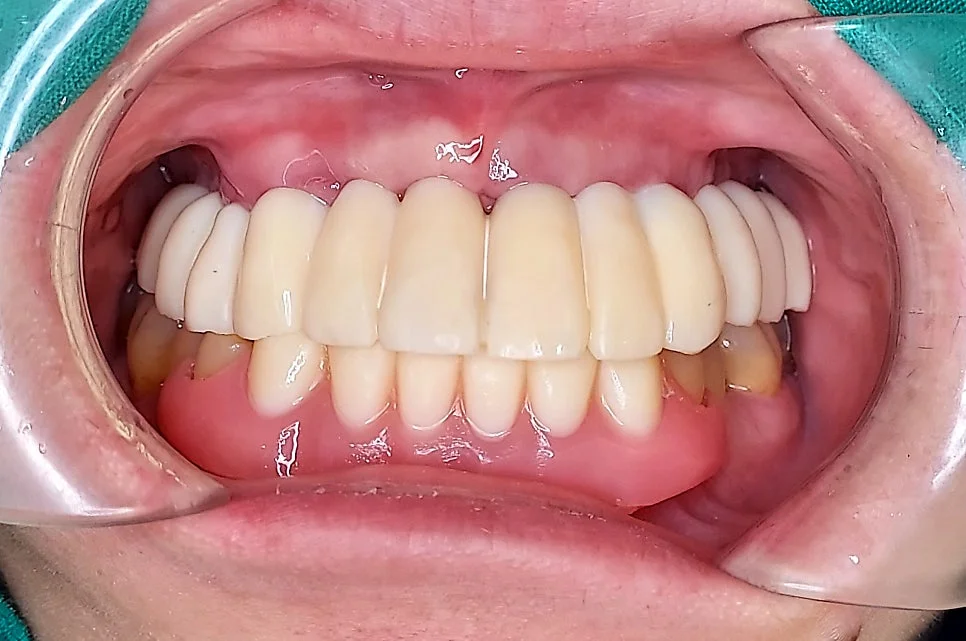

보철 과정 – Before / 임시 / 최종 완성

대략 2~4개월 정도의 임플란트 유착 기간 후에 보철물 제작에 들어가게 됩니다. 임시 치아를 상당 기간 사용한 후 최종 보철물을 제작합니다.

남아 있는 잇몸을 기준으로 치아의 높이를 결정하고, 위아래 입술의 위치에 따라 전후방 위치를 결정하고, 웃는 모습을 기준으로 치아를 이상적으로 배열하고, 최대한 자연스러운 색상으로 환자분과 결정합니다.